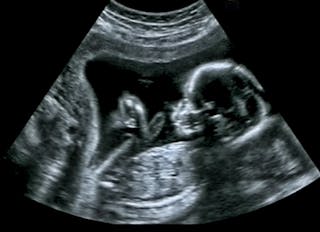

ultrassom

ultrassom usa ondas sonoras para gerar uma imagem médica da anatomia humana, e não tem efeitos prejudiciais conhecidos. A frequência de ultrassom é maior do que as frequências de onda sonora que podem ser detectadas pela audição humana. As ondas sonoras só podem viajar através de um meio, então um gel à base de água precisa ser aplicado na pele, o que permite que o ultrassom seja transmitido do transdutor (ou sonda-a coisa que se moveu sobre a área que está sendo escaneada) para o corpo.

o ultrassom reflete ondas sonoras diferentemente de todos os diferentes tecidos dentro do corpo, quanto mais denso é o tecido, mais ondas sonoras são refletidas e retornadas ao transdutor. Quando o tecido é menos denso, parte das ondas sonoras serão devolvidas ao transdutor e parte do ultrassom será transmitida através deste tecido até atingir um tipo diferente de tecido e o processo continuar (parcialmente refletido e parcialmente transmitido).

quando ondas de ultrassom retornam ao transdutor, as ondas sonoras são convertidas em um sinal elétrico, que é então digitalizado e reconstruído como uma imagem. A imagem é formada calculando a distância de onde as ondas sonoras refletidas interagiram com o tecido e o transdutor, e é calculada sabendo que no tecido humano, o ultrassom viaja a aproximadamente 1.540 metros por segundo.

para muitos exames de ultra-sons, os pacientes são convidados a suster a respiração, de modo que os órgãos internos permanecem ainda enquanto a imagem está ocorrendo. Podem também ser convidados a deslocar-se para determinadas posições.

além de fornecer informações estruturais sobre como a anatomia é organizada, o ultrassom tem o benefício adicional de fornecer informações biomecânicas e funcionais, como também pode imagem em tempo real e observar os músculos e tendões se movendo.

a imagiologia por ultra-sons tem duas aplicações importantes. A primeira é na gravidez e a segunda é para ver se músculos e tendões estão de alguma forma danificados.